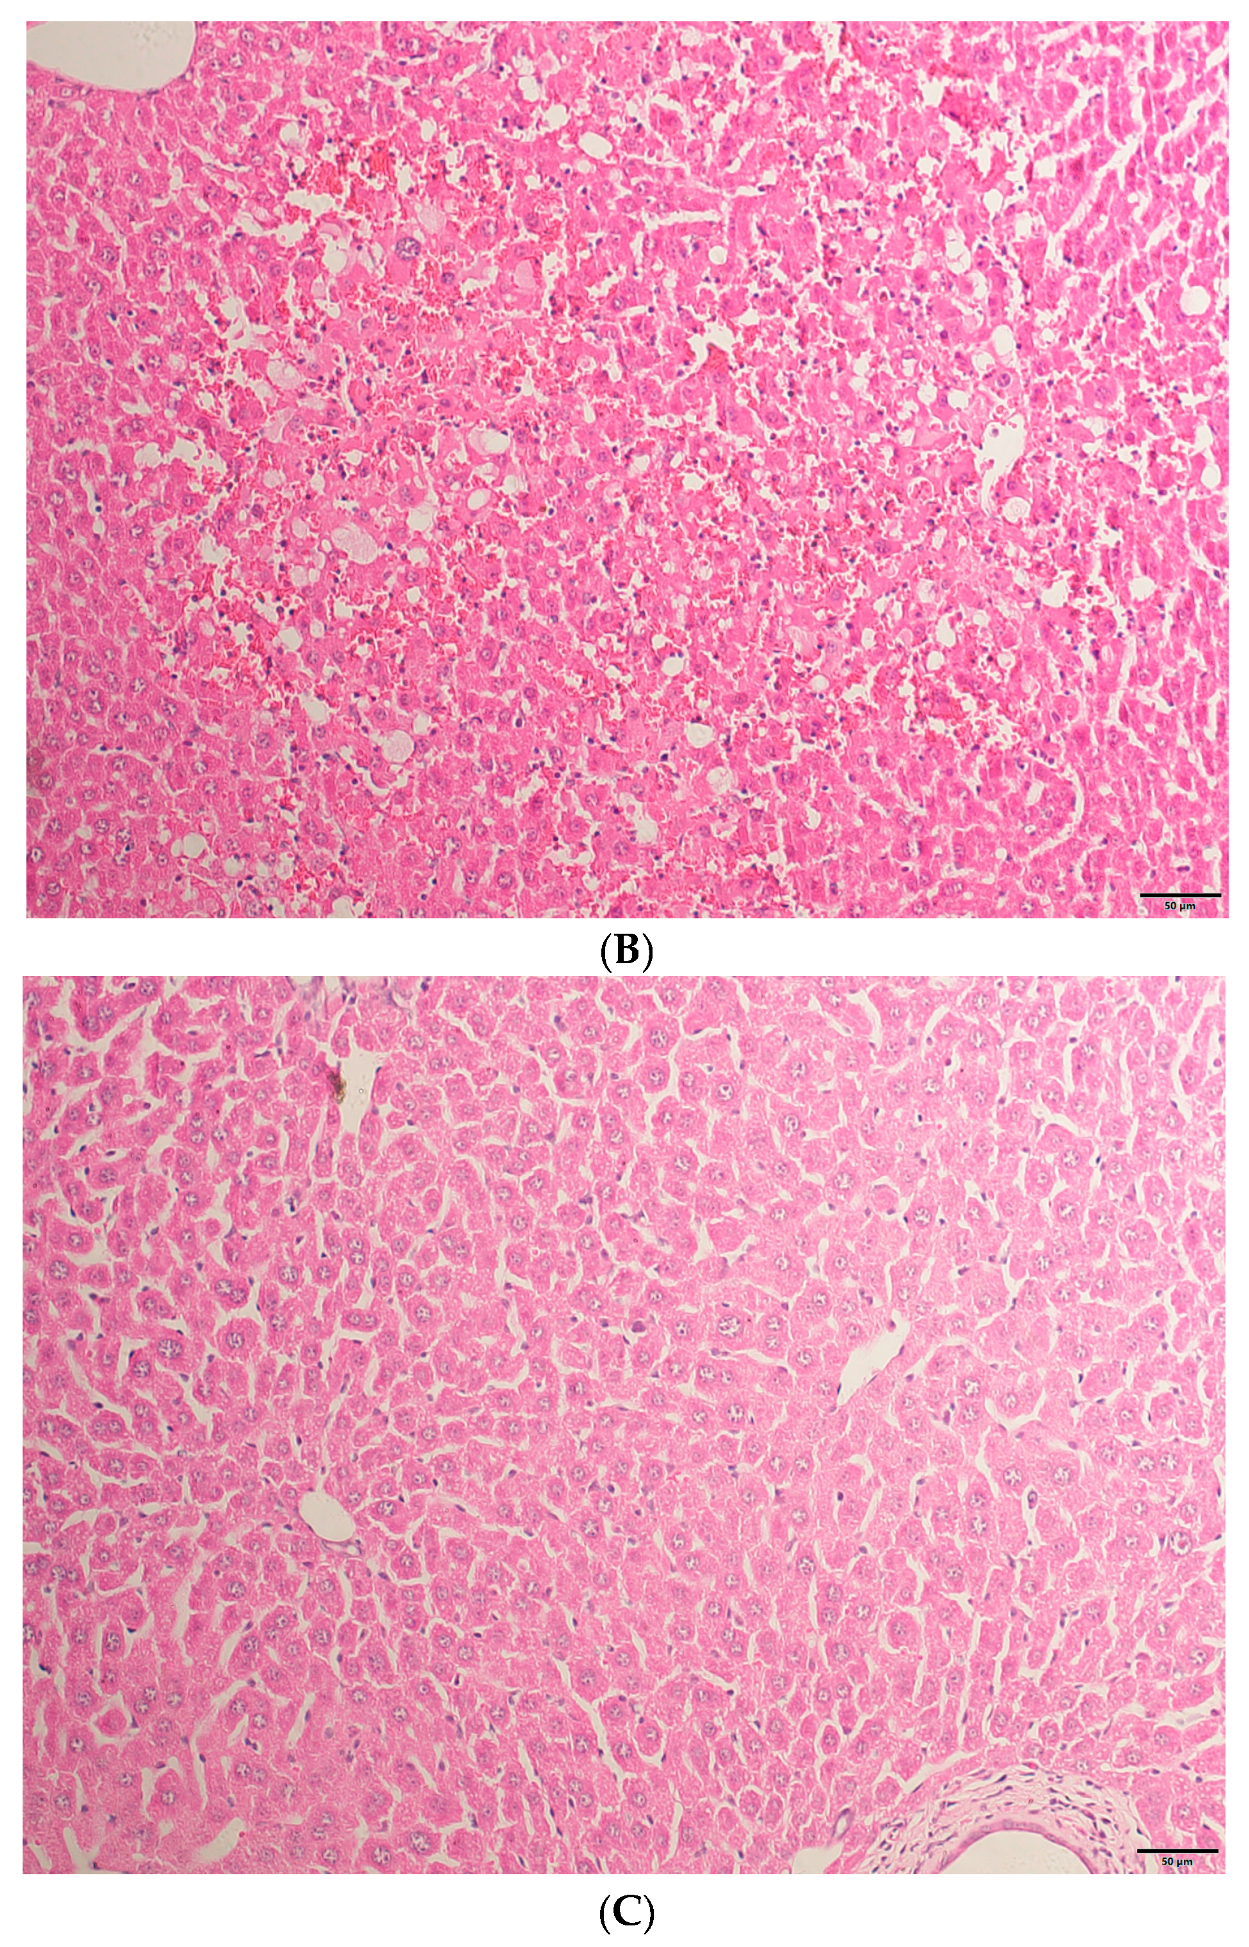

2.1. HE Staining Results